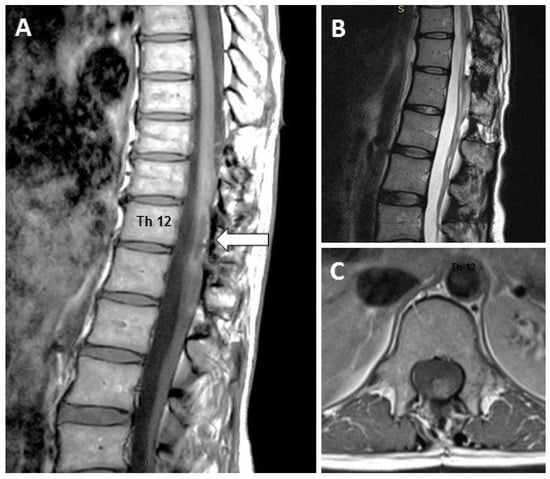

3.1. Case 1

3.2. Case 2